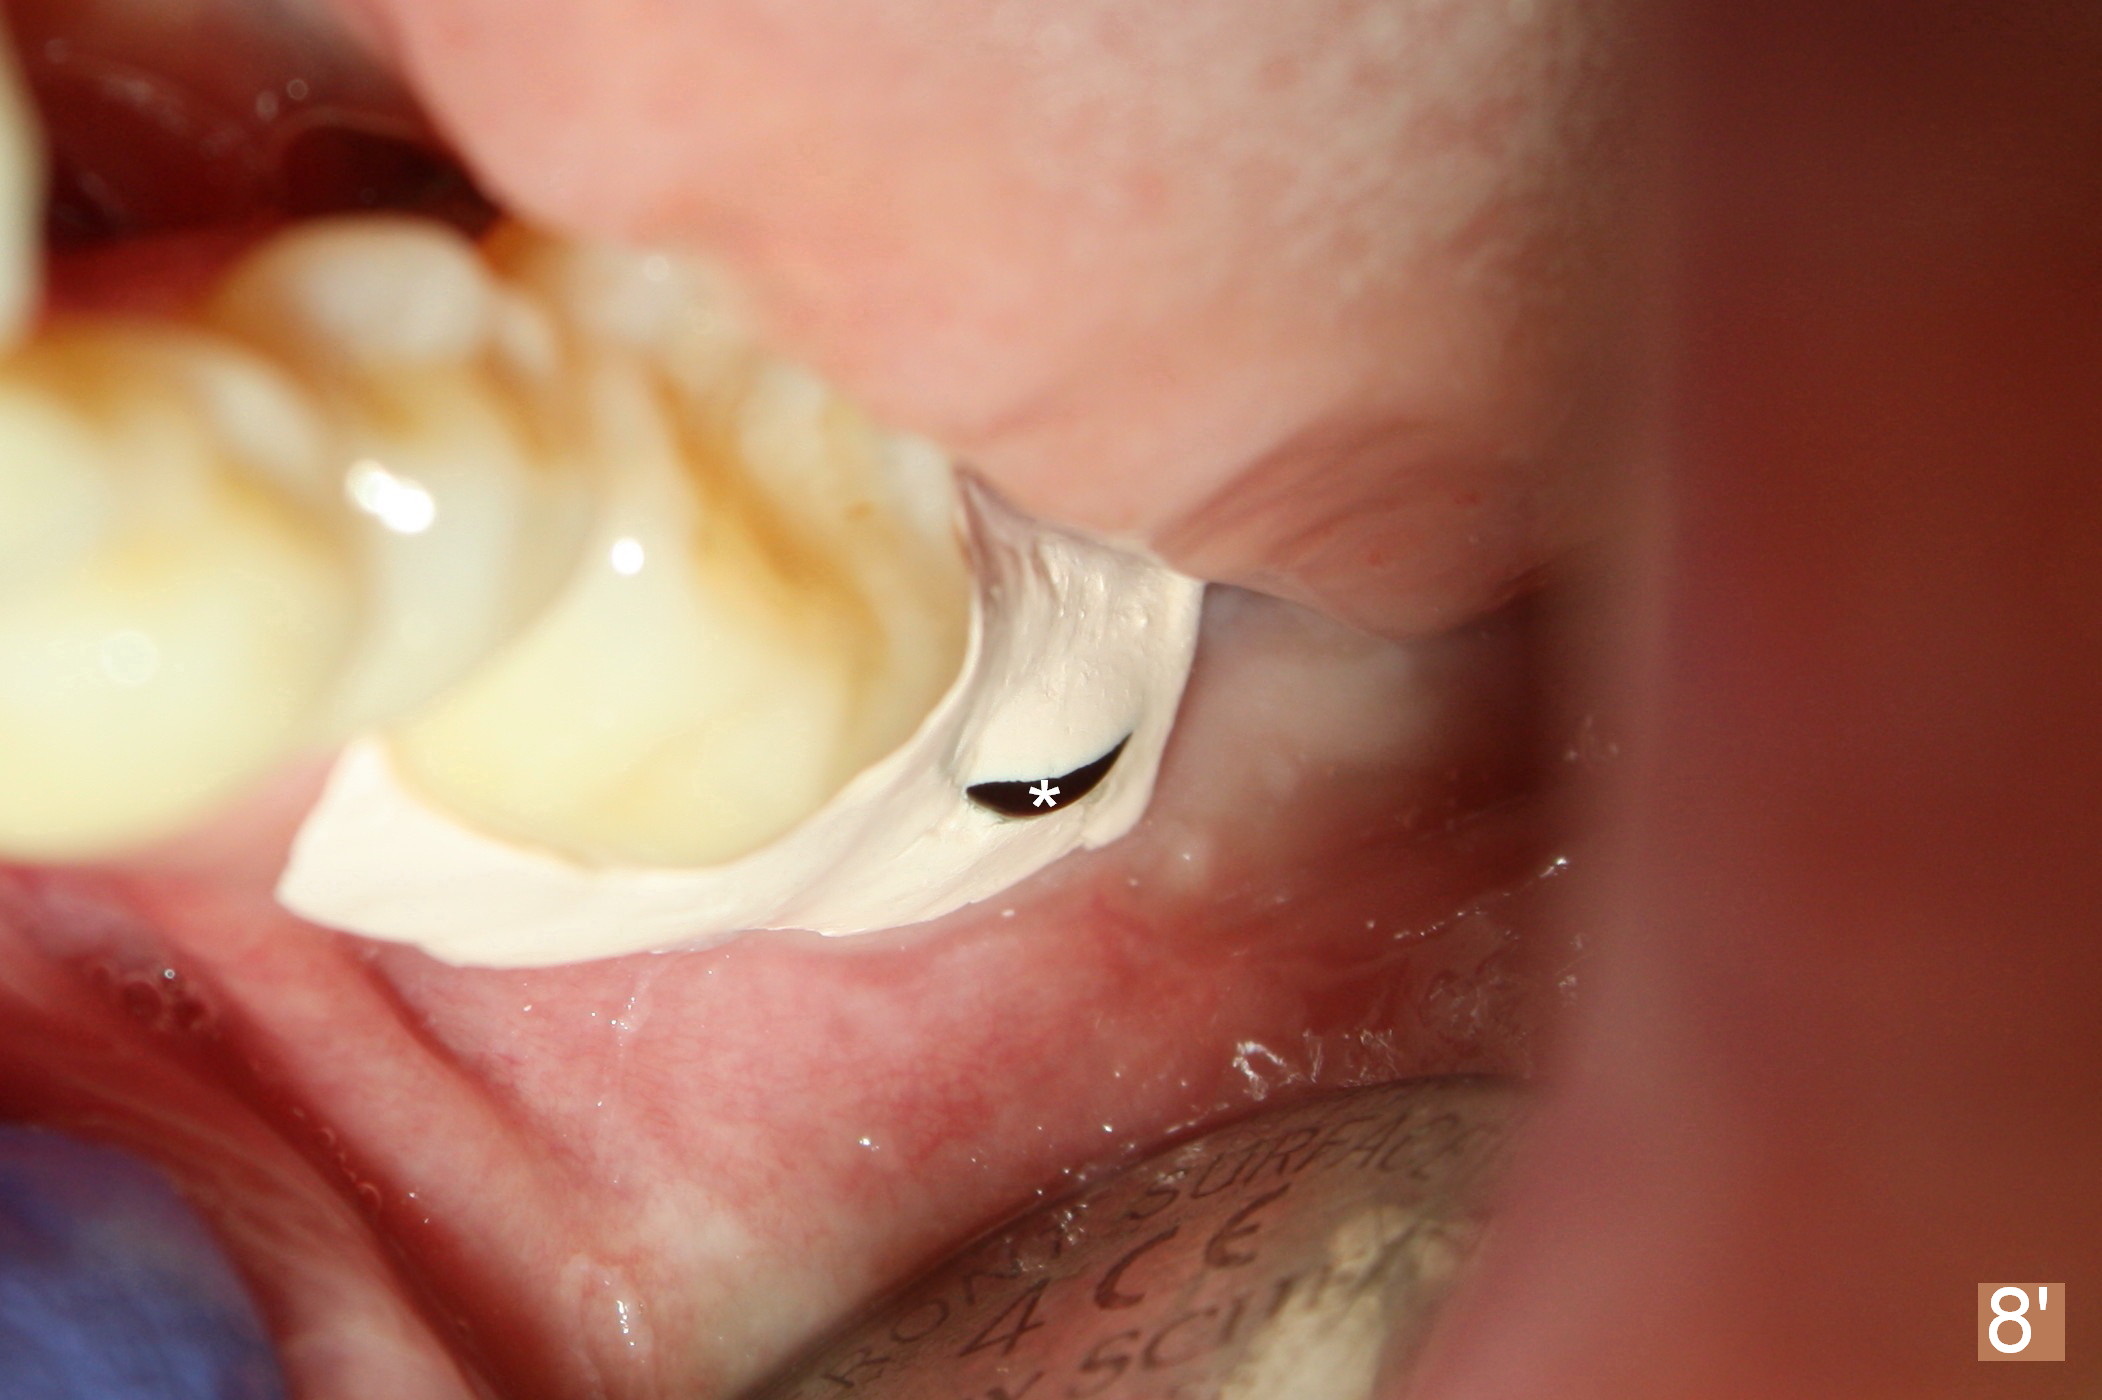

A 48-year-old lady is a dental phobic, requesting extraction of the lower left 2nd molar (Fig.1).   She returns for implant placement 9 months post extraction (Fig.2).  The ridge is mildly to moderately atrophic.  It appears that a 5x12 mm implant is appropriate for the site (Fig.3).  For safety, osteotomy is initiated at the depth of 10 mm; it appears that there is enough height for a 12 mm implant (Fig.4).  The depth is controlled by drill stopper (Fig.5 S).  Finally a 5x12 mm implant is apparently safely placed (Fig.6).  A healing abutment is placed and the incision is sutured with 4-0 Chromic gut (Fig.7).  Perio dressing is applied around the healing abutment for wound protection (Fig.8).  It appears that the healing abutment (Fig.8': *) helps stabilize the perio dressing, which remains in place 1 week postop.  When the perio dressing is removed, the wound around the healing abutment is healing (Fig.9).  There is no bone loss around the implant 3 months postop (Fig.10 (H: healing abutment), or 16 months postop (i.e., 9 months post cementation, Fig.11,12).  The patient complains of pain when she chews with the implant crown, but pain stops whenever she does not bite.  Percussion does not elicit any discomfort.  The gingiva is healthy.  There is possibility of the buccal plate being thin or the lingual plate being perforated in the submandibular fossa.  If the discomfort remains the same next 6 months, CBCT will be prescribed.